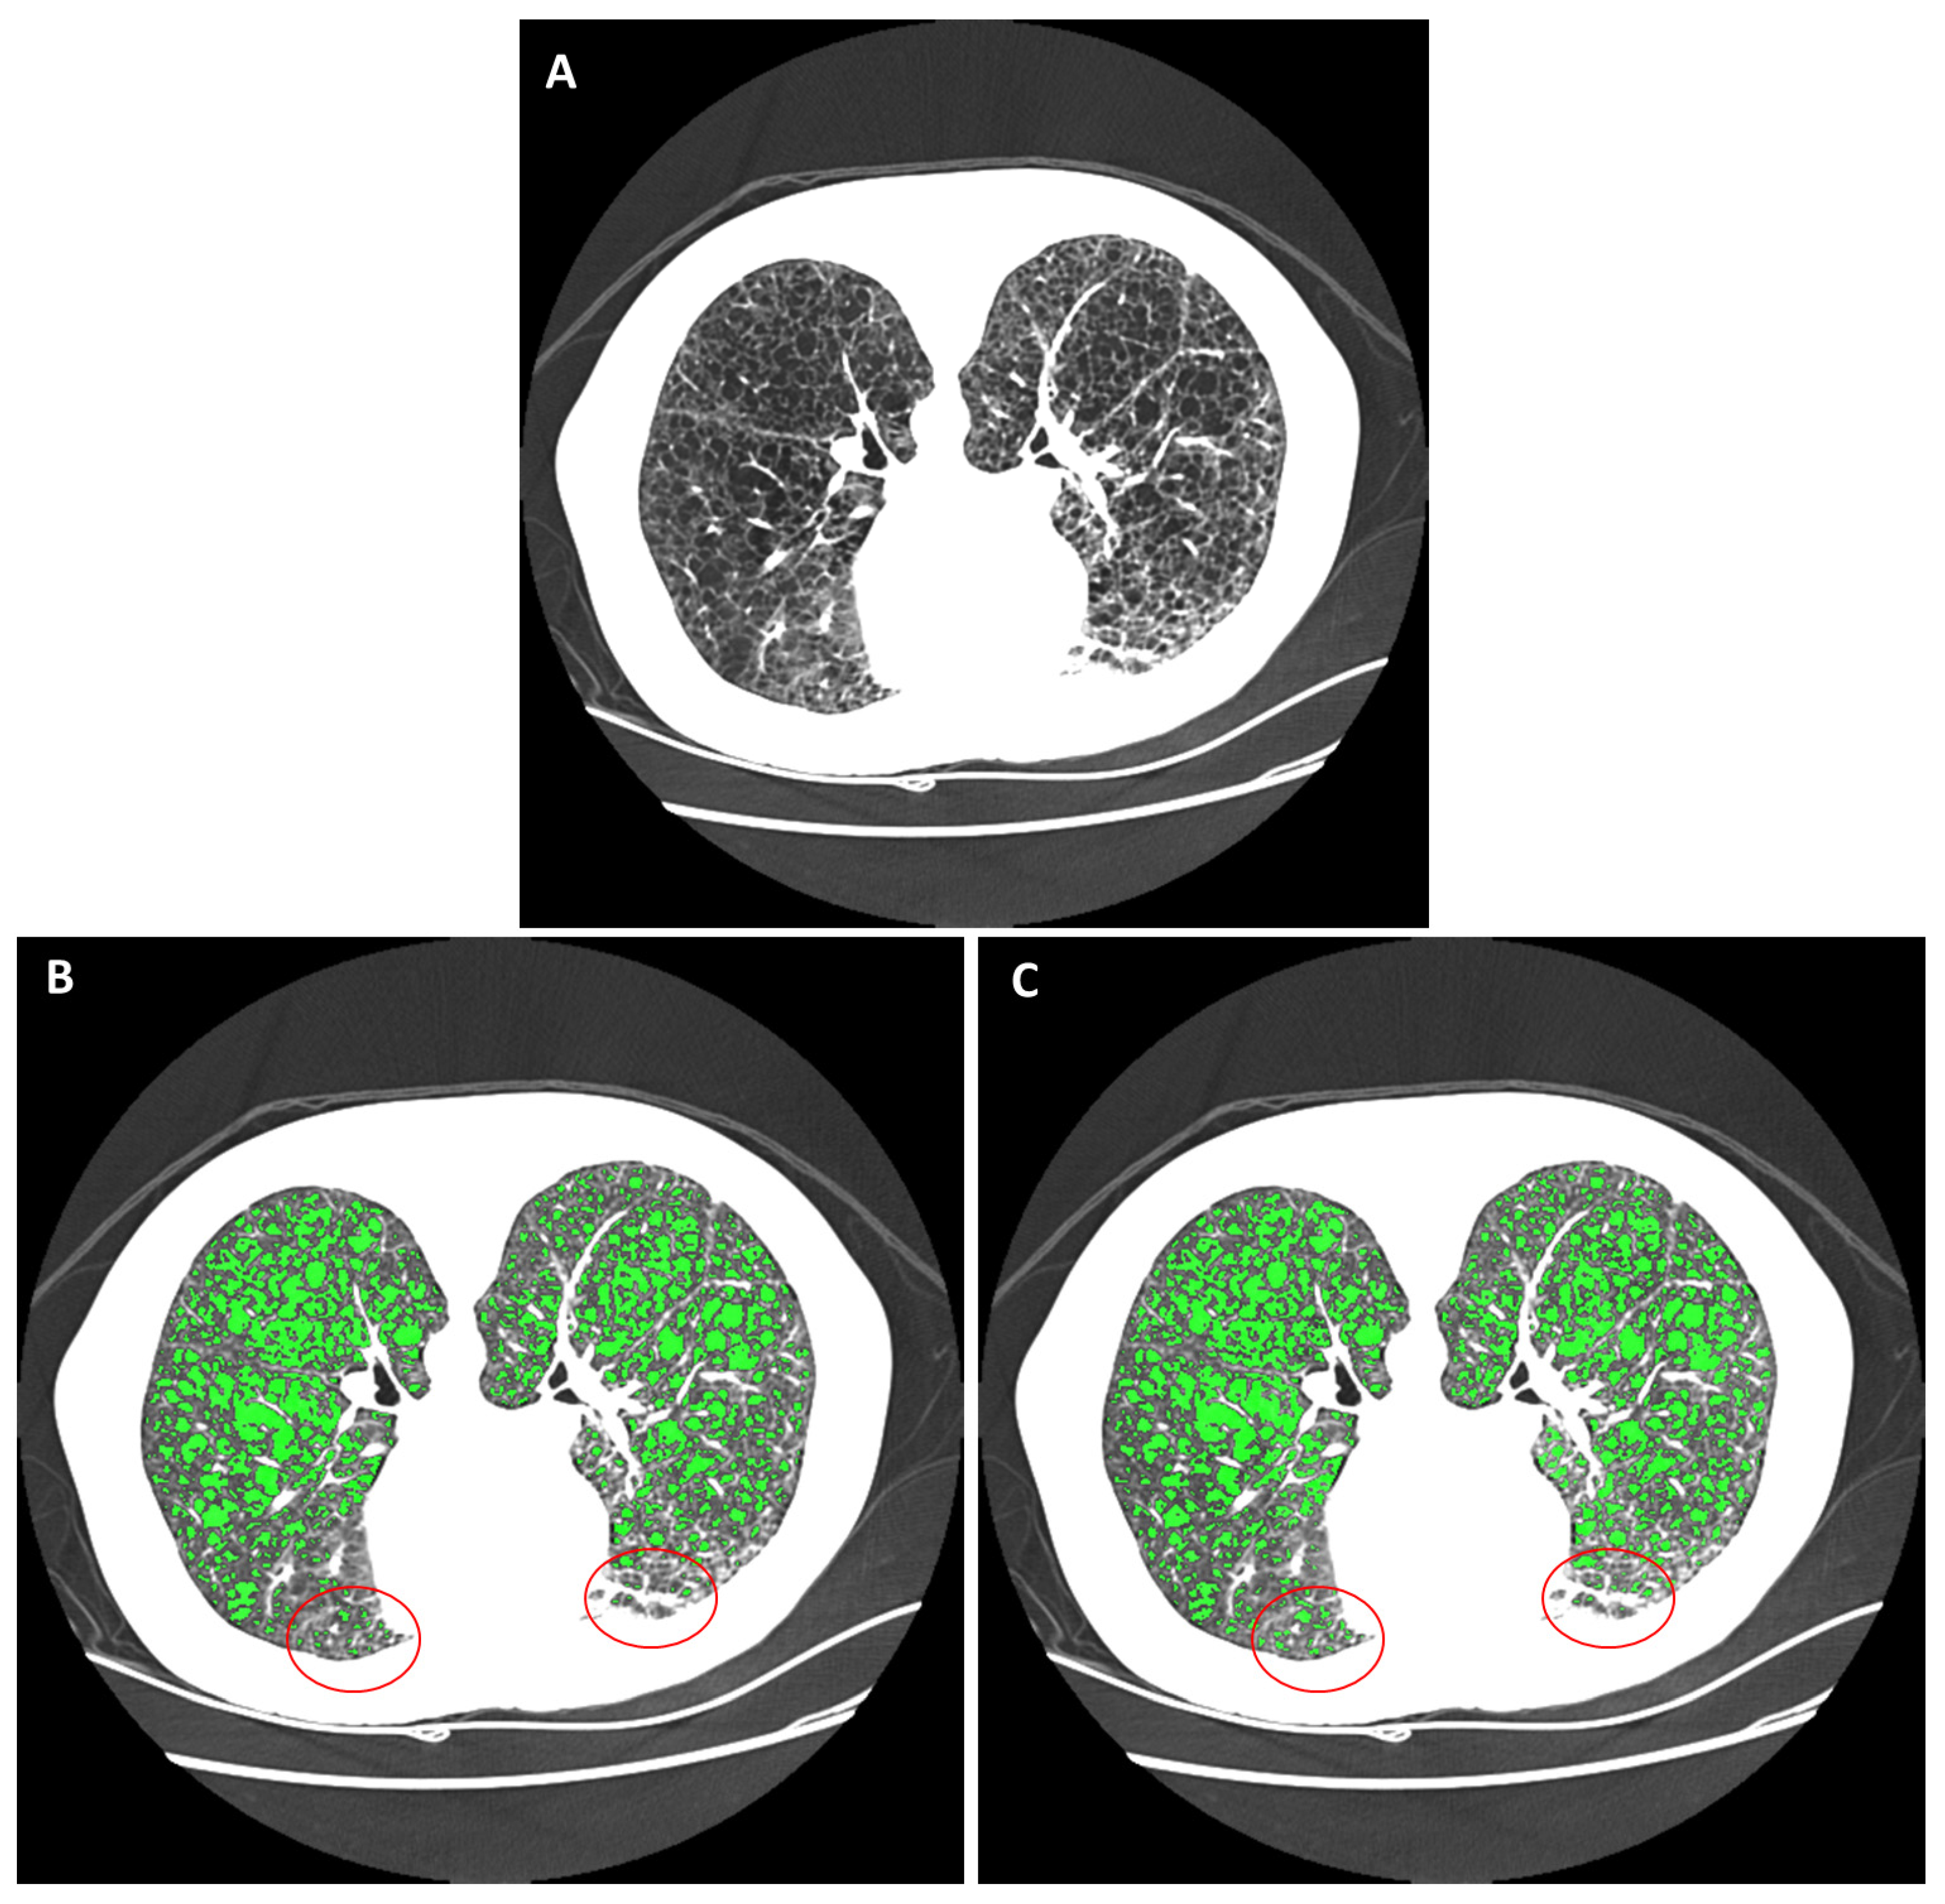

2.4. Automated Cyst Segmentation